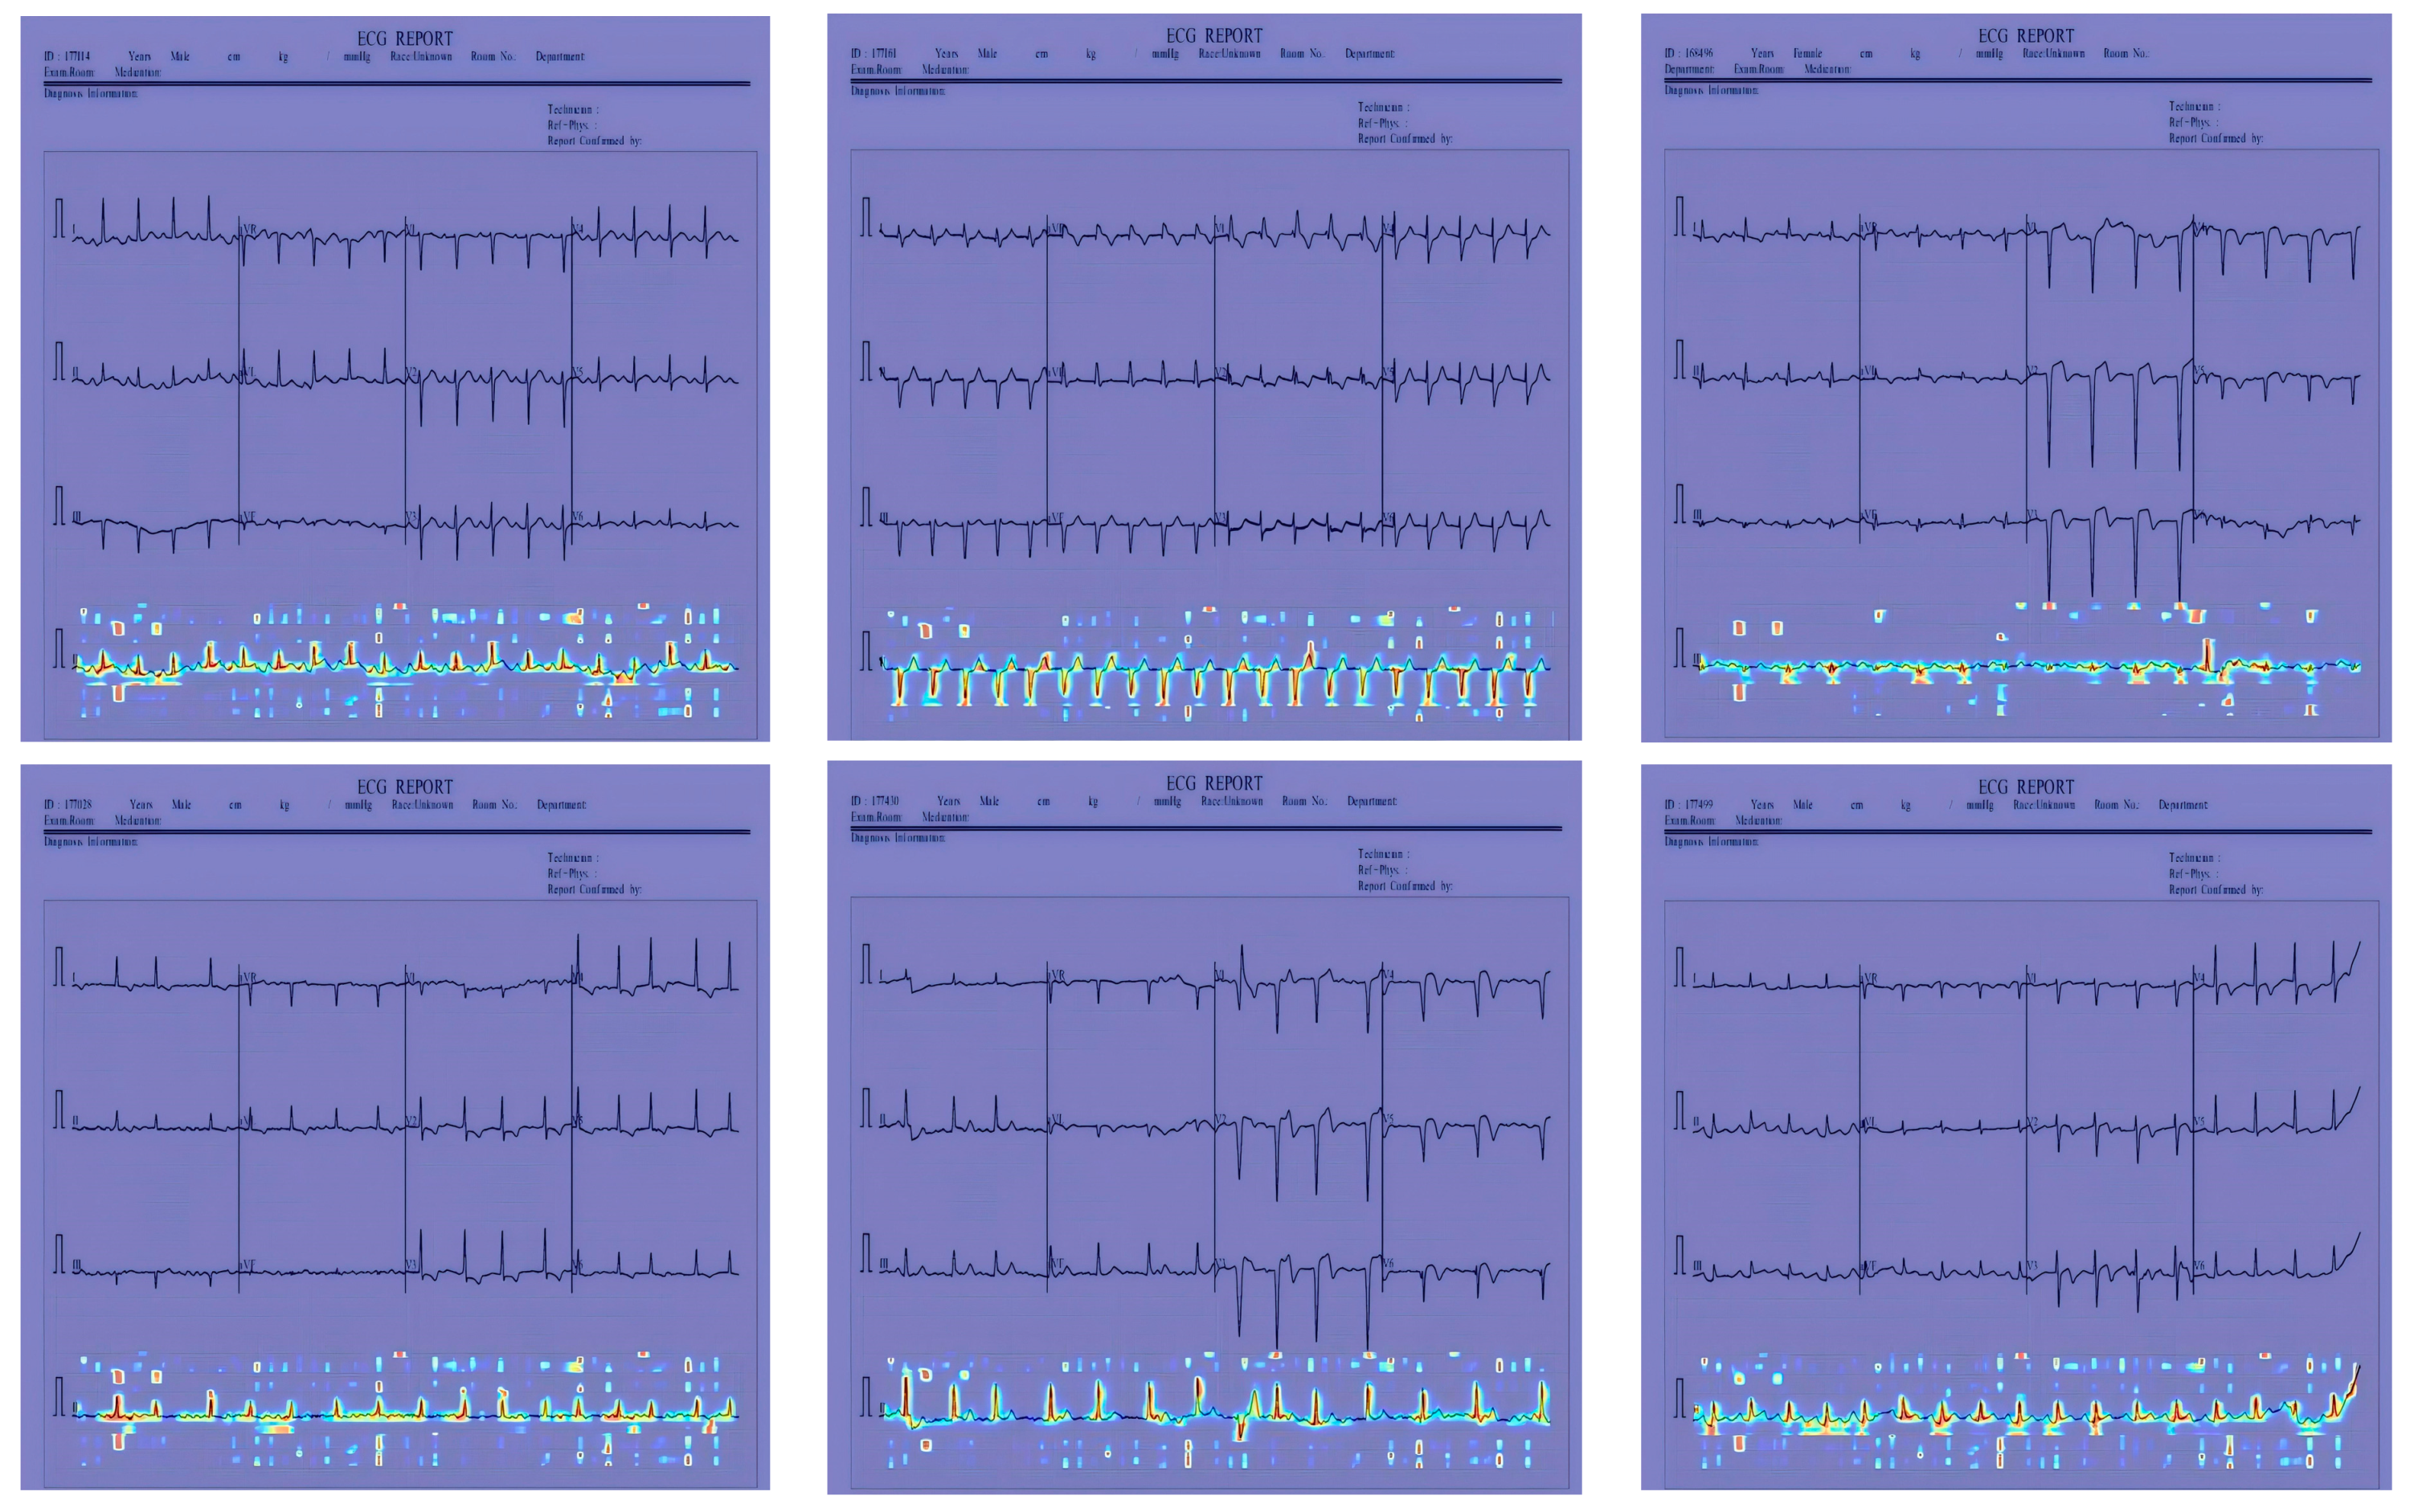

The ECG image dataset utilized in this work is sourced from the information from a total of 271 patients, which has been collected from the Cardiology Departments of Chittagong Medical College and Dhaka Medical College Hospital. A sample of ECG raw data can be seen in Figure 6 and the ECG image dataset containing several ECG images is shown in Figure 7. The dataset comprises 1231 images, categorized into four different classes, including ECG HB, history-MI, MI-ECG, and normal-ECG. HB stands for the ECG images of patients who have an abnormal heartbeat, MI stands for the ECG images of myocardial infarction patients, history-MI stands for the ECG images of patients who have a history of myocardial infarction, and normal stands for normal peoples’ ECG images. The dataset aims to help the scientific community to conduct research for all kinds of cardiac pathologies and cardiovascular diseases.

In Figure 12, Figure 13 and Figure 14, the performance comparison of the feature visualization of ECG data using YOLOv7, YOLOv9, and our proposed method Mamba-RAYOLO is shown. The ECG data were selected randomly from different categories, and ECG ID:168500, ECG ID:177430, and ECG ID:168605 were selected. When dealing with ECG image feature visualization and heat map generation, compared with YOLOv7 and YOLOv9, it can be seen that the use of our proposed method Mamba-RAYOLO has a clearer contour and contrast, which is more able to highlight the key features of ECG signals, the data are more complete and comprehensive, and it has the strongest robustness and best performance compared with other methods. Figure 15 shows the feature visualization effect on ECG data with our proposed method Mamba-RAYOLO, which can capture the ECG signal data comprehensively and accurately, highlight the key features, there is no information loss phenomenon, and the color distribution is clear.

Figure 12. Comparison of feature visualization of ECG ID:168500. (a) Feature visualization of YOLOv7; (b) feature visualization of YOLOv9; (c) feature visualization of our proposed method.

Sensors 24 05087 g012

Figure 13. Comparison of feature visualization of ECG ID:177430. (a) Feature visualization of YOLOv7; (b) feature visualization of YOLOv9; (c) feature visualization of our proposed method.

Sensors 24 05087 g013

Figure 14. Comparison of feature visualization of ECG ID:168605. (a) Feature visualization of YOLOv7; (b) feature visualization of YOLOv9; (c) feature visualization of our proposed method.

Sensors 24 05087 g014